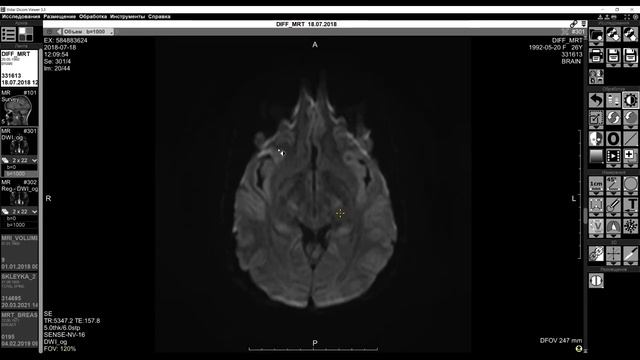

Обучающее видео "Интерфейс МРТ" смотреть онлайн

07:07

Обучающее видео "Интерфейс МРТ"

Эзотерический ум 99 просмотров